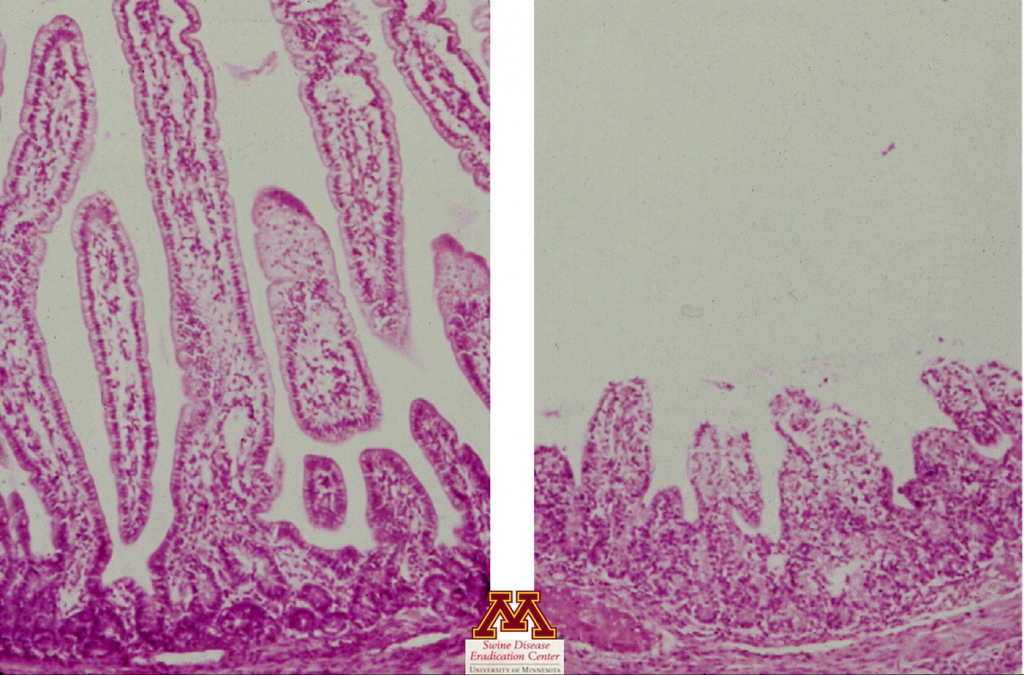

Histopatologia

- Avalia a presença de lesões teciduais (atrofia das vilosidades do intestino delgado) que podem sugerir fortemente a presença de doença.

- Confirma atrofia das vilosidades sugerindo enterite viral

- Positivo: Confirmação da doença, mas não da causa da doença.

- Negativo: Negativo ou lesões não são detectadas se a amostra errada for testada ou feita muito tempo após a infecção.